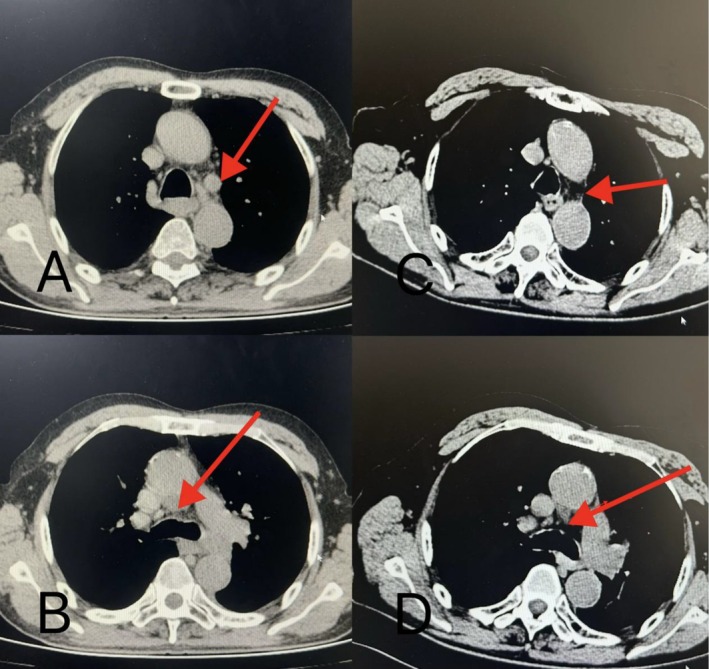

Case presentation: We present the case of an 83-year-old patient with stage IV lung adenocarcinoma treated with four cycles of intravenous Tirelizumab and two cycles of intratumoral Tirelizumab via tracheoscopy. The patient achieved partial clinical remission, with tumor lesions continuing to shrink upon follow-up by August 24, 2024. No treatment-related adverse reactions were observed, and the patient's immune function remained normal.